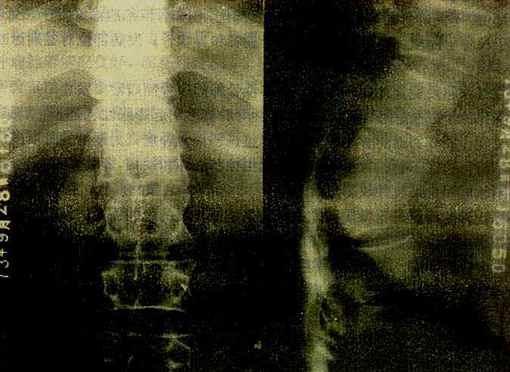

图2-1-22 脊椎结核

胸12与腰1椎体破坏、融合,两椎体间不见椎间隙,于该处有后突变形,

于右侧可见腰大肌脓肿,并有钙化

椎体结核主要引起骨松质的破坏。由于骨质破坏和脊柱承重的关系,椎体塌陷变扁或呈楔形。由于病变开始多累及椎体的上下缘及邻近软骨板,较早就引起软骨板破坏,而侵入椎间盘,使椎间隙变窄,甚至消失和椎体互相嵌入融合而难于分辨(图2-1-22)。病变广泛。常出现后突变形。病变在破坏骨质时可产生大量干酪样物质流入脊柱周围软组织中而形成冷性脓肿。腰椎结核干酪样物质顺一侧或两侧腰大肌引流,称为腰大肌脓肿,表现为腰大肌轮廓不清或呈弧形突出。胸椎结核的脓肿在胸椎两旁,形成椎旁脓肿,表现为局限性梭形软组织肿胀,边缘清楚。在颈椎,则使咽后壁软组织增厚,并呈弧形前突,侧位上易于观察。冷性脓肿较久可有不规则形钙化